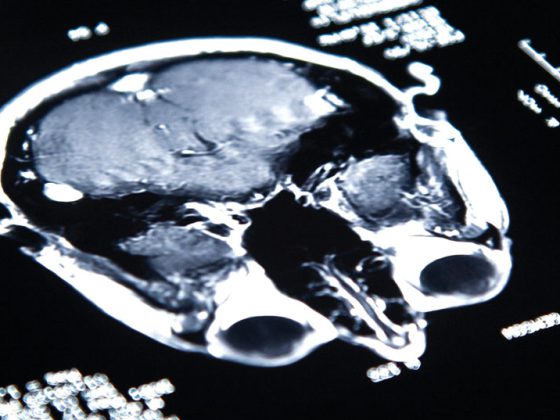

gehirn_istock-186871490

Neue Indikationen für die Immunonkologie?

• Kongressberichte

• Neurologie

• Onkologie